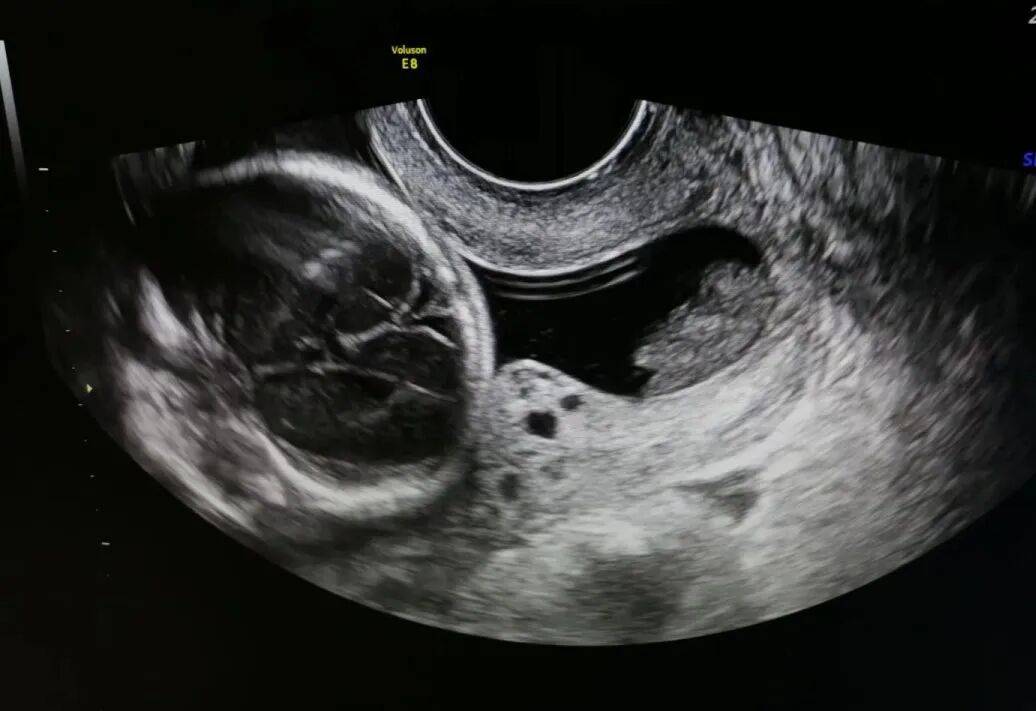

怀孕23周,本该是相对平稳的时期,王女士来院进行四维彩超检查,却发现了“异常警报”。

超声影像清晰显示:宫颈内口已呈漏斗状开放,前后径约6mm,宫颈管扩张7mm,仅剩的宫颈管闭合段长度仅约18mm。诊断为"双胎妊娠合并宫颈机能不全"。